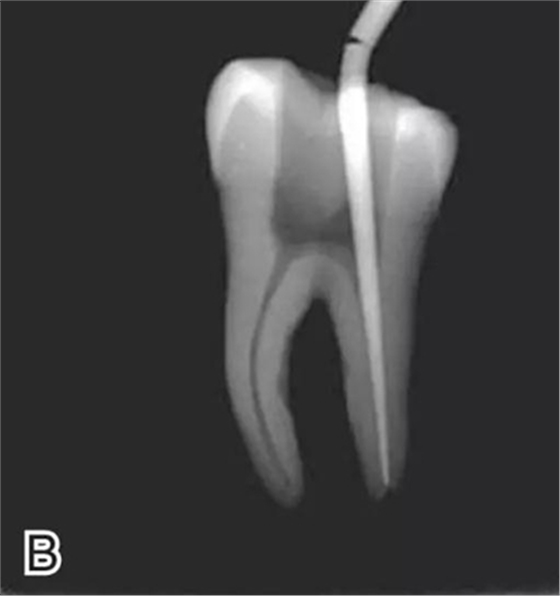

2、選擇垂直加壓器

選擇的小號垂直加壓器應(yīng)能自由到達(dá)距根尖4~5 mm(有學(xué)者提出3~4 mm)的位置并能輕微接觸根管壁;中號垂直加壓器應(yīng)能自由到達(dá)距根尖7~8 mm的位置并能輕微接觸根管壁;大號垂直加壓器應(yīng)能自由到達(dá)距根尖10~11 mm的位置并能輕微接觸根管壁。用橡皮片做好標(biāo)記(圖2)。

圖2 選擇垂直加壓器,A.試垂直加壓器 B.垂直加壓器在根內(nèi)的位置